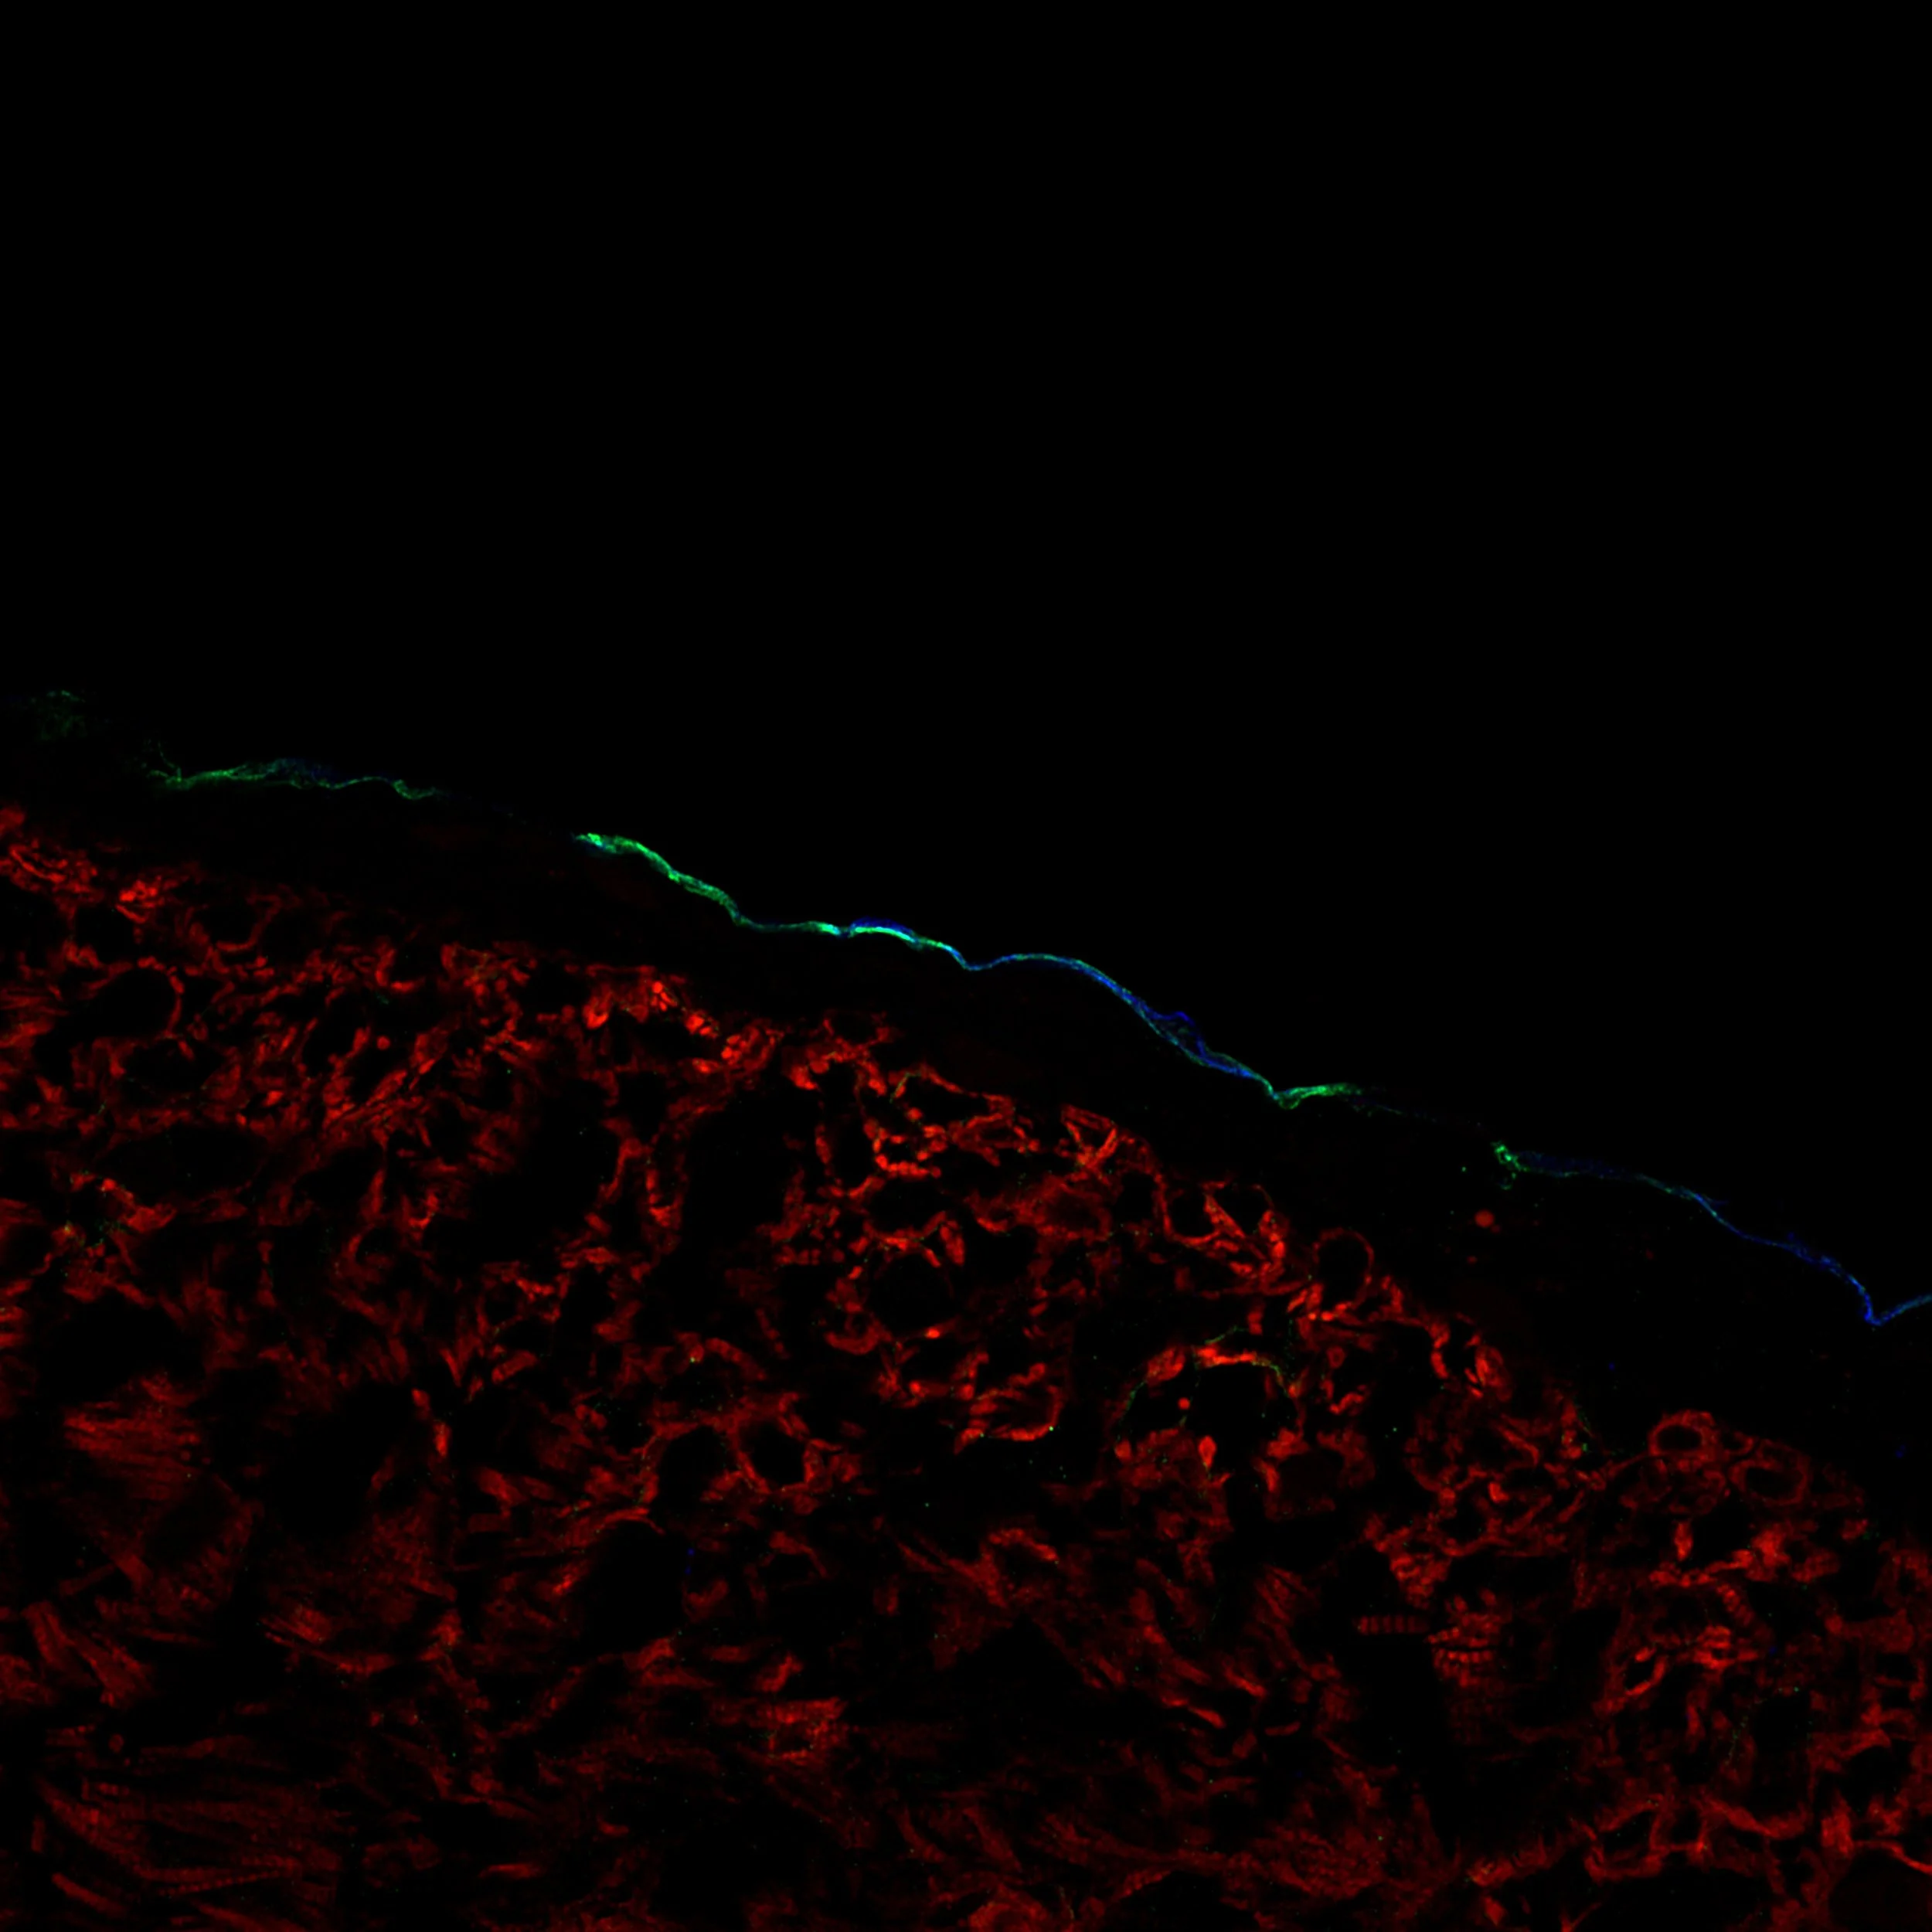

The epicardium on the outside of the myocardium in the human fetal heart. Here we see epicardial cells highlighted in blue and green by keratin 19 (KRT19) and periostin (POSTN), and cardiomyocytes highlighted in red by cardiac troponin (cTnT).